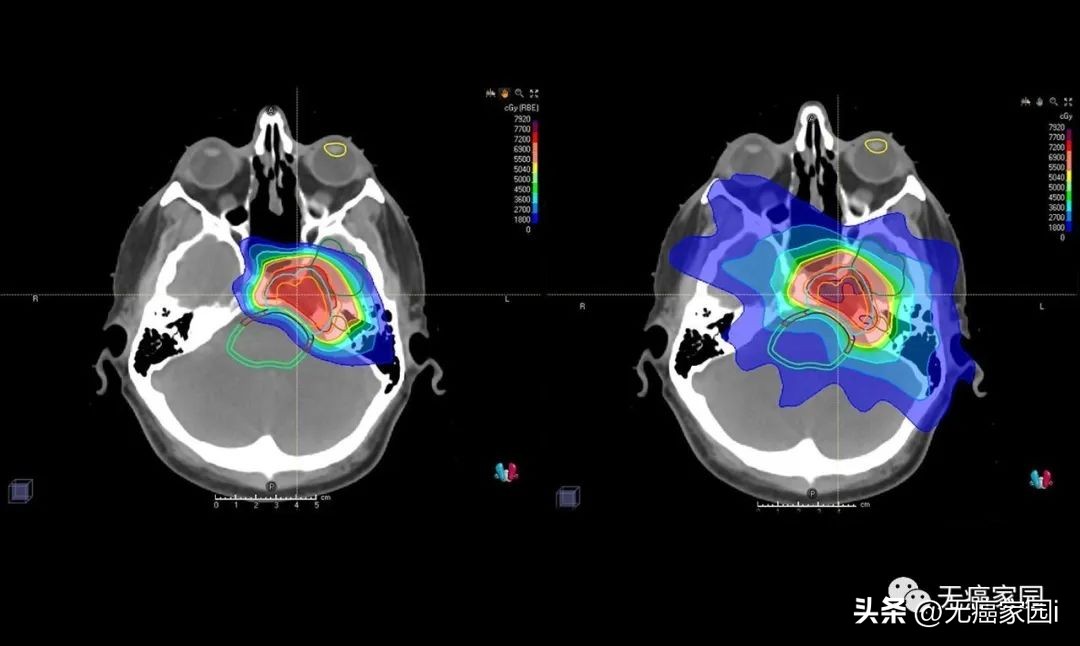

研究结果显示,与传统的光子放射疗法(EBRT)相比,PBRT具有物理优势。在下图的典型病例示意图中, 传统光子治疗在眼内靠近肿瘤的部位剂量较大,而且后眼眶和脑内肿瘤远端的剂量也明显高于质子治疗。

左图为常规光子束治疗,右图为质子束治疗

图中患者的脑部扫描显示质子(左)如何专门针对肿瘤,而对周围组织和结构的辐射最小,传统的光子辐射(右)会损坏周围的组织和结构